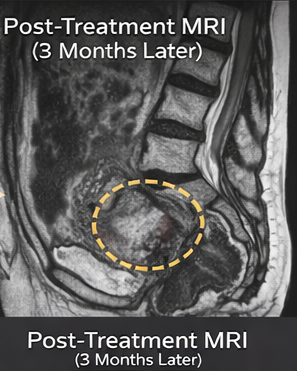

At three months post-treatment, clinical examination showed complete resolution of the cervical lesion. MRI of the pelvis demonstrated significant tumor regression with no residual disease. At six-month follow-up, the patient remained asymptomatic, with no evidence of local recurrence or distant metastasis. Menopausal symptoms related to pelvic irradiation were managed conservatively.